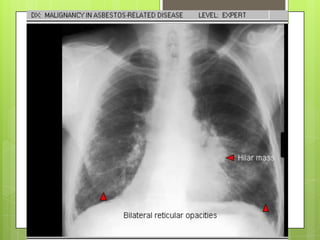

RADIOGRAFÍA Y ESPIROMETRÍA

 Imágenes lineales en campos inferiores y

engrosamiento de pleura parietal 

calcifican (>20 años)

COMPLICACIONES

 Carcinoma broncogénico: adenoCa, Ca

de células pequeñas o Ca epidermoide

 Mesotelioma maligno 5-8%

 Derrame pleural “benigno” (precoz)

 Insuficiencia respiratoria

 Cor pulmonale